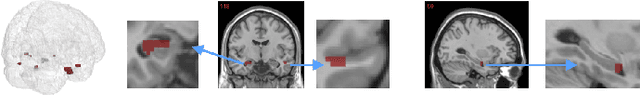

Abstract:The prediction and selection of lesion features are two important tasks in voxel-based neuroimage analysis. Existing multivariate learning models take two tasks equivalently and optimize simultaneously. However, in addition to lesion features, we observe that there is another type of feature, which is commonly introduced during the procedure of preprocessing steps, which can improve the prediction result. We call such a type of feature as procedural bias. Therefore, in this paper, we propose that the features/voxels in neuroimage data are consist of three orthogonal parts: lesion features, procedural bias, and null features. To stably select lesion features and leverage procedural bias into prediction, we propose an iterative algorithm (termed GSplit LBI) as a discretization of differential inclusion of inverse scale space, which is the combination of Variable Splitting scheme and Linearized Bregman Iteration (LBI). Specifically, with a variable the splitting term, two estimators are introduced and split apart, i.e. one is for feature selection (the sparse estimator) and the other is for prediction (the dense estimator). Implemented with Linearized Bregman Iteration (LBI), the solution path of both estimators can be returned with different sparsity levels on the sparse estimator for the selection of lesion features. Besides, the dense the estimator can additionally leverage procedural bias to further improve prediction results. To test the efficacy of our method, we conduct experiments on the simulated study and Alzheimer's Disease Neuroimaging Initiative (ADNI) database. The validity and the benefit of our model can be shown by the improvement of prediction results and the interpretability of visualized procedural bias and lesion features.

Abstract:Neuroimage analysis usually involves learning thousands or even millions of variables using only a limited number of samples. In this regard, sparse models, e.g. the lasso, are applied to select the optimal features and achieve high diagnosis accuracy. The lasso, however, usually results in independent unstable features. Stability, a manifest of reproducibility of statistical results subject to reasonable perturbations to data and the model, is an important focus in statistics, especially in the analysis of high dimensional data. In this paper, we explore a nonnegative generalized fused lasso model for stable feature selection in the diagnosis of Alzheimer's disease. In addition to sparsity, our model incorporates two important pathological priors: the spatial cohesion of lesion voxels and the positive correlation between the features and the disease labels. To optimize the model, we propose an efficient algorithm by proving a novel link between total variation and fast network flow algorithms via conic duality. Experiments show that the proposed nonnegative model performs much better in exploring the intrinsic structure of data via selecting stable features compared with other state-of-the-arts.